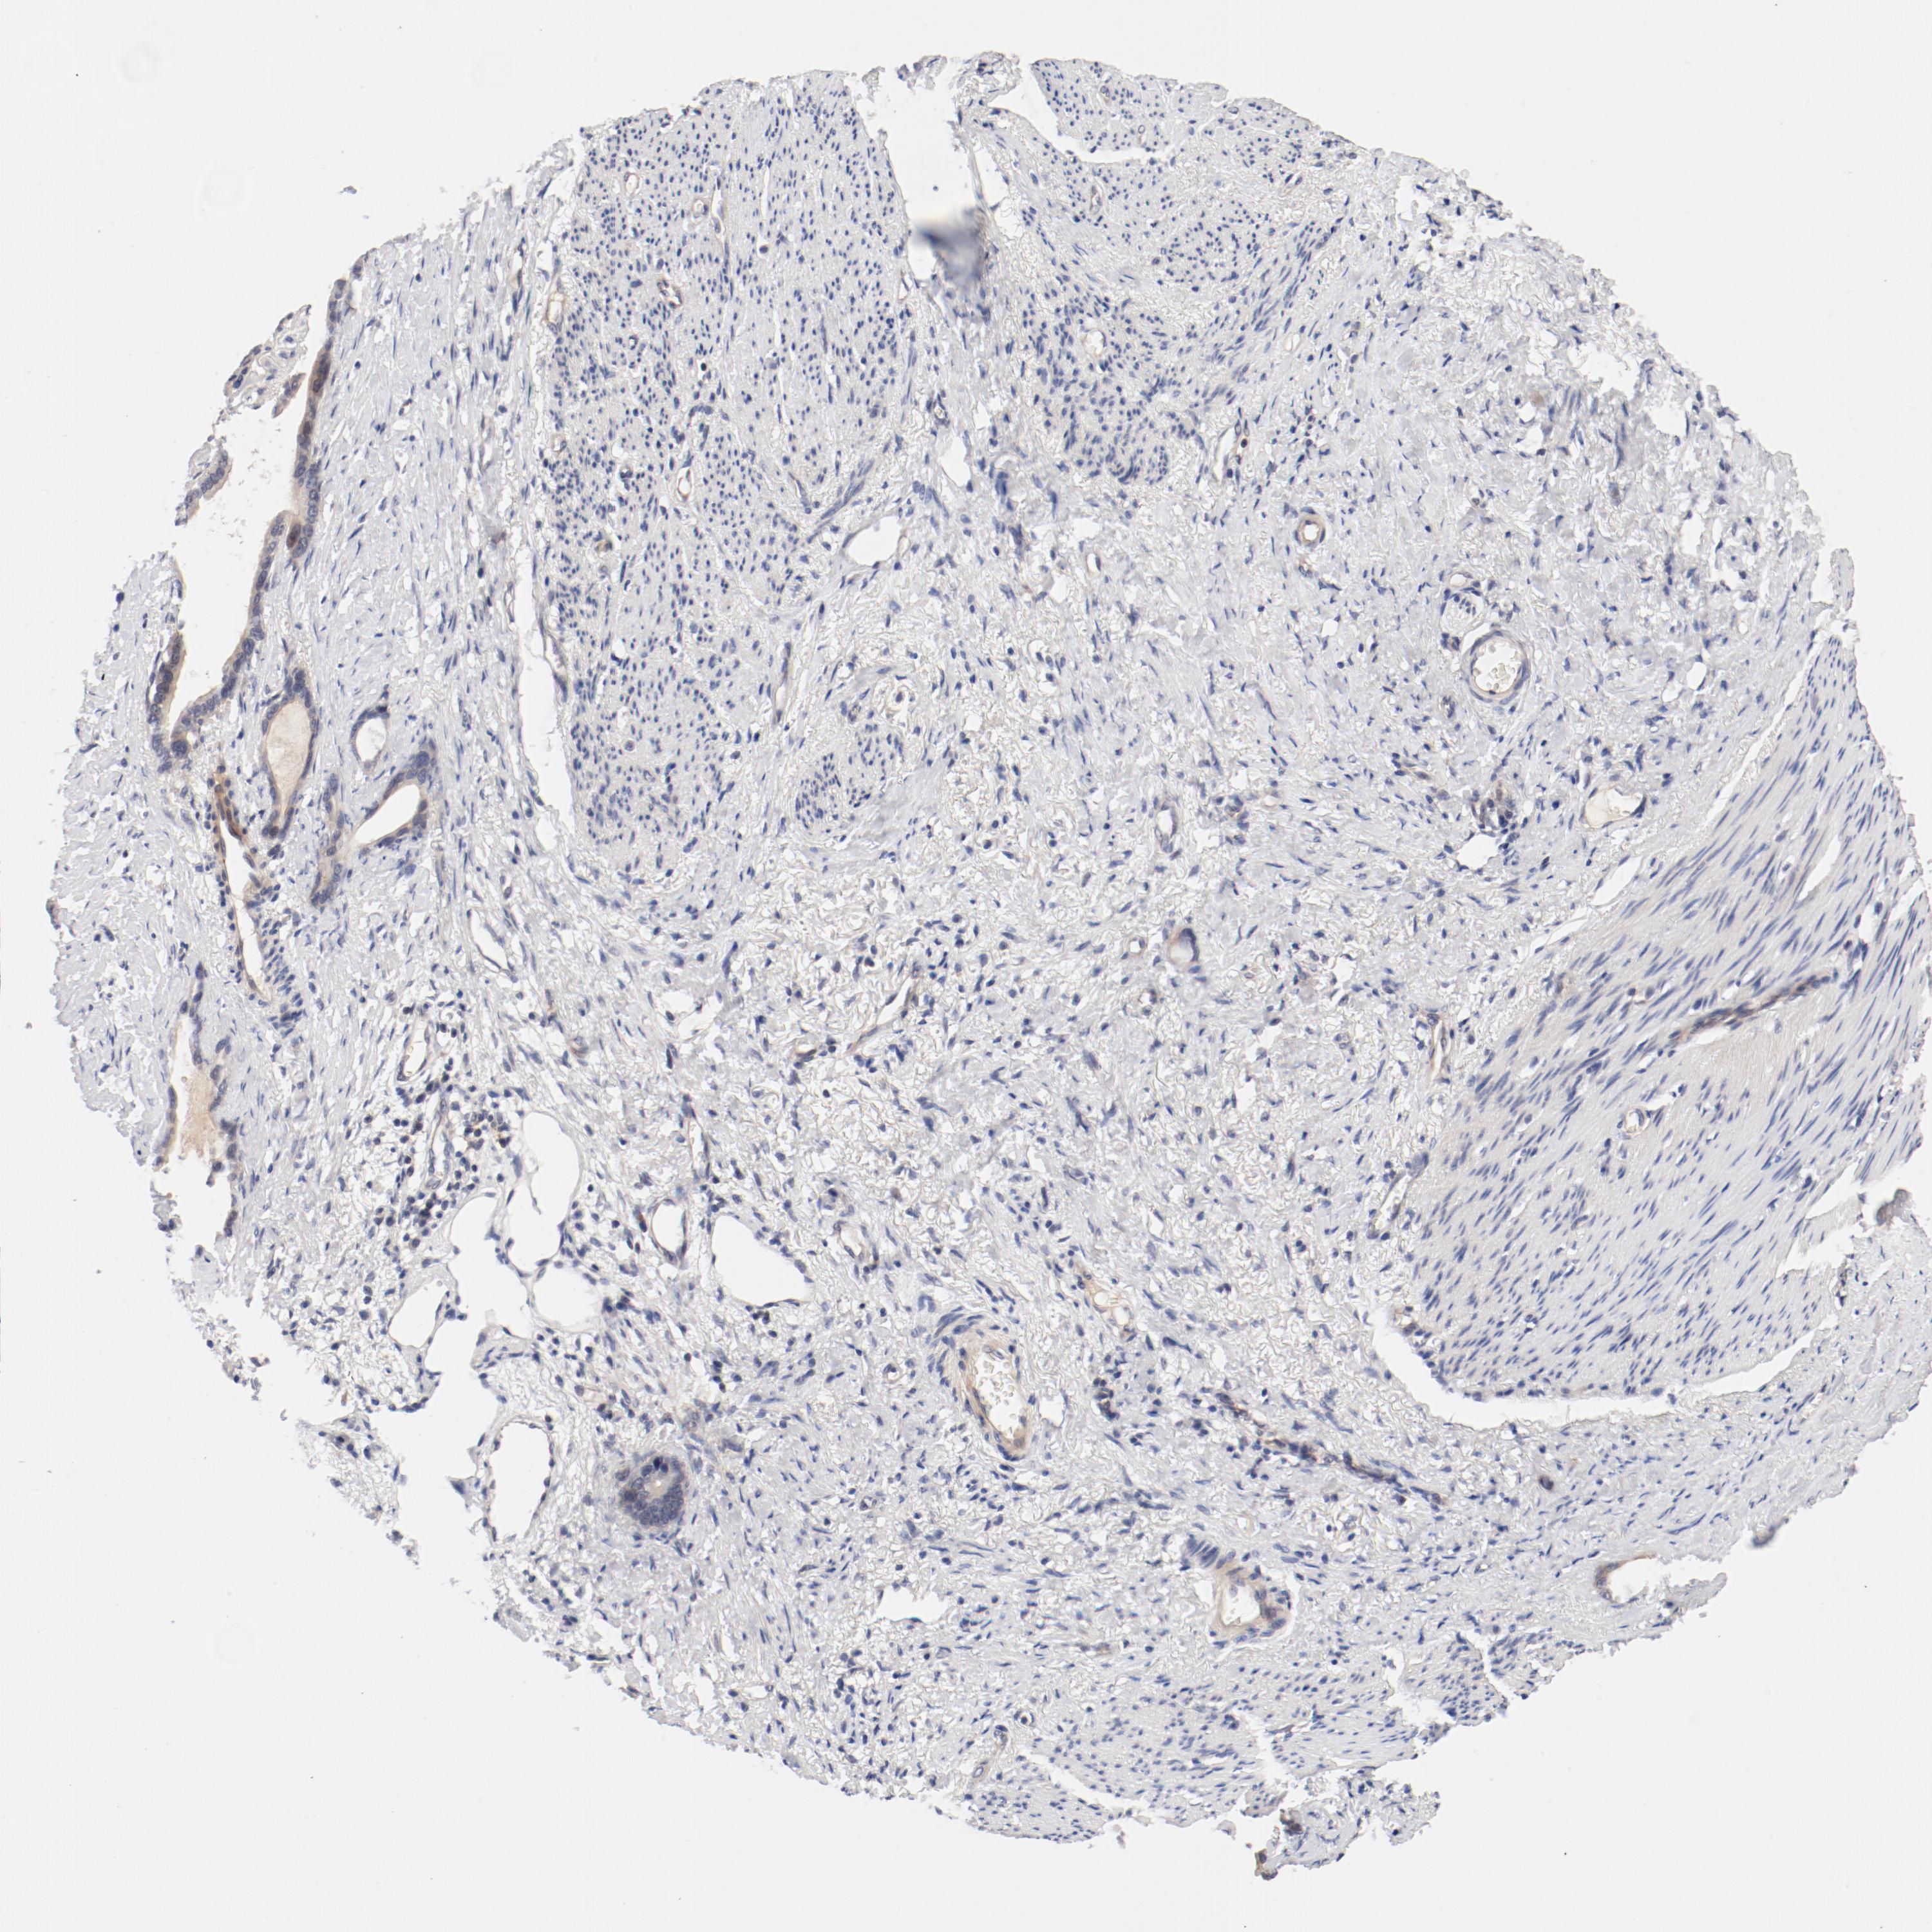

STOMACH CANCER - Protein expressioni

A mouse-over function shows sample information and annotation data. Click on an image to view it in a full screen mode. Samples can be filtered based on level of antibody staining by selecting one or several of the following categories: high, medium, low and not detected. The assay and annotation is described here.

Note that samples used for immunohistochemistry by the Human Protein Atlas do not correspond to samples in the TCGA dataset.

Antibody stainingi

Antibody staining in the annotated cell types in the current human tissue is reported as not detected, low, medium, or high, based on conventional immunohistochemistry profiling in selected tissues. This score is based on the combination of the staining intensity and fraction of stained cells.

Each image is clickable and will lead to virtual microscopy that enables deeper exploration of all samples and also displays staining intensity scores, fraction scores and subcellular localization as well as patient and tissue information for each sample.

Antibody HPA003866

Staining

High

Medium

Low

Not detected

Intensity

Strong

Moderate

Weak

Negative

Quantity

>75%

75%-25%

<25%

None

Location

Nuclear

Cytoplasmic/membranous

Cytoplasmic/membranous,nuclear

Adenocarcinoma, NOS

Adenocarcinoma, High grade